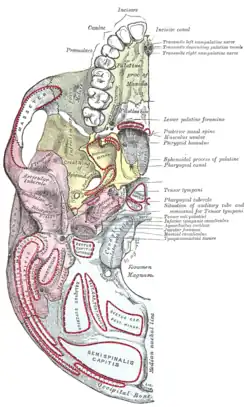

Occipital bone. Outer surface. Base of skull. Inferior surface.

Base of skull. Inferior surface.